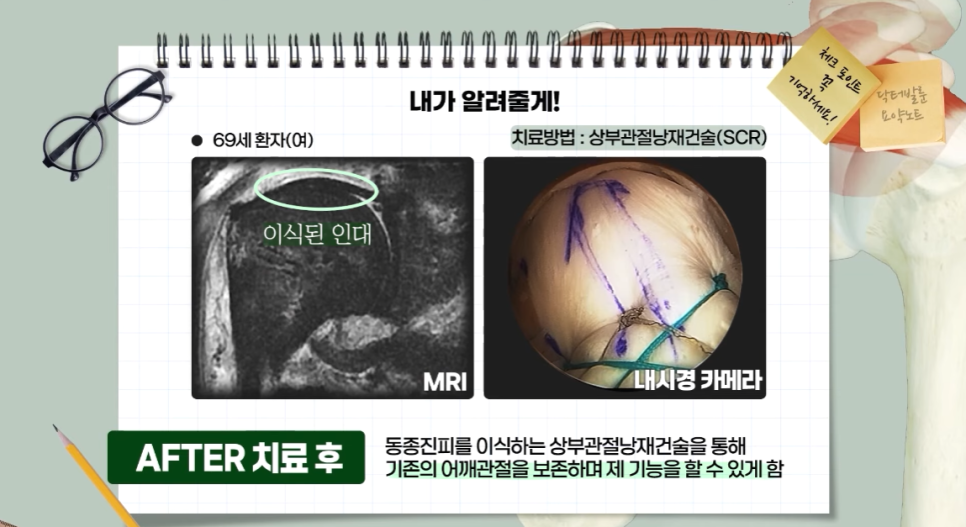

회전근개파열을 늦게 진단받았거나 일반 회전근개 봉합술 적응증이 안 되는 경우, 어깨 재수술을 해야 하는 경우에 시도할 수 있는

어깨 치료방법으로 세바른병원의 상부관절낭재건술 치료방법이 있는데요, 비어있는 회전근개 범위가 커서 봉합술이 불가능하다 판단될 경우에도 서초동 정형외과 세바른병원의 상부관절낭재건술을 통해 동종진피,인조인대를 사용하여 비어있는 회전근개 부위를 재건할 수 있습니다.

상부관절낭재건술(SCR)치료는 손상받은 어깨 회전근개 힘줄 부위에 기증받은 “동종진피(인조인대)를 이식하여, 손상된 관절을 다시 살려내고 본인의 관절을 그대로 유지하며 어깨를 정상적으로 사용할 수 있게 해주는 최소침습 관절내시경 치료”입니다.

상부관절낭재건술은 일본의 Mihata 등이 고안한 수술법으로 최초에는 환자 본인의 대퇴근막을 허벅지에서 떼어내어 손상되어 없어져 버린 회전근개를 대신하여 어깨관절에 이식하는 치료법으로 시작하였으나, 이런 방법은 이식근막을 떼어낸 부위인 허벅지에 상처 및 통증이 추가로 발생하며, 이식건을 채취하고 다듬는데 걸리는 수술시간이 추가되고, 채취건의 질과 양을 예측하기 어려워, 최근에는 이런 자가대퇴근막을 대신하여 ⭐이식 거부반응을 제거한 동종진피(ADM; Acellular Dermal Matrix; 인공인대)를 기증받아 사용하여 내시경 상부관절낭재건술을 진행하고 있습니다.